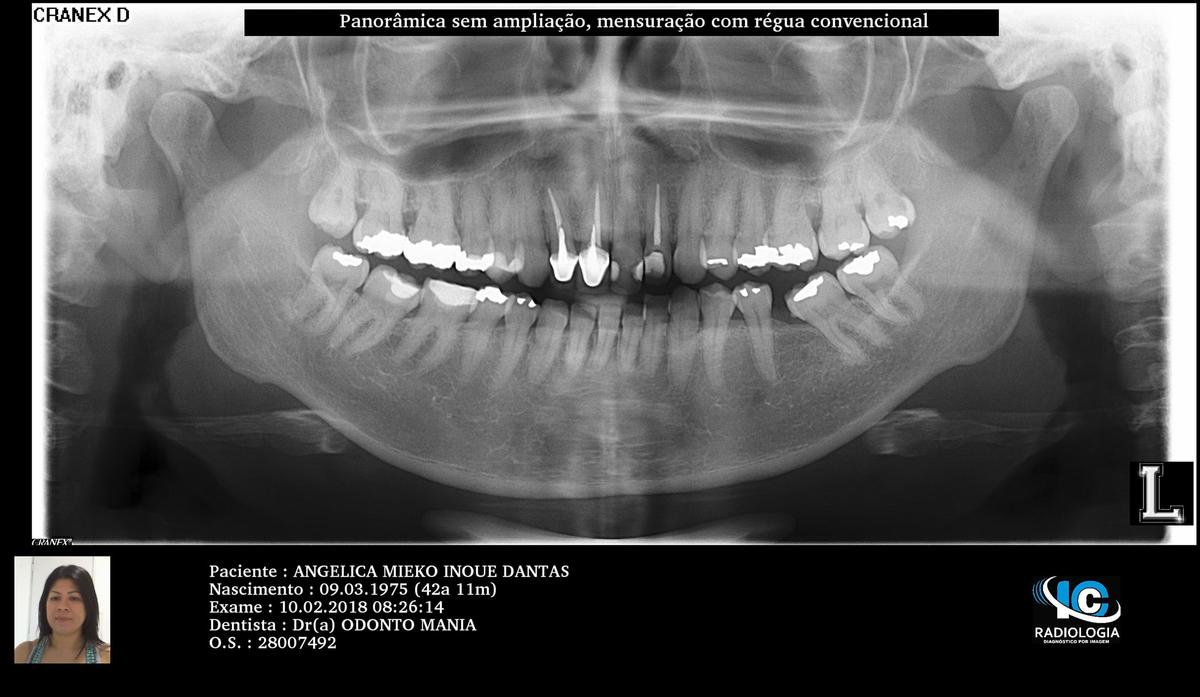

LENTES DE CONTATO DENTAIS EM PORCELANA

A.M.I.D.